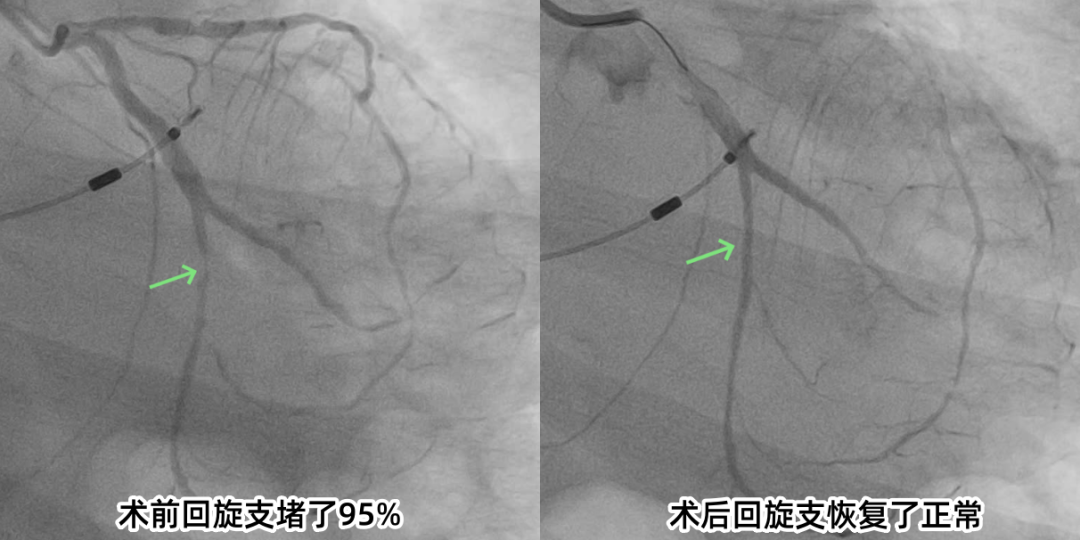

“胸闷痛 2 天,以为是年纪大了扛一扛就过去,没想到是心肌梗死!”回忆起入院时的情景,91岁的高大爷仍心有余悸。作为一名非ST段抬高型心肌梗死患者,他的肌钙蛋白指标持续异常,冠状动脉造影显示回旋支中段弥漫性狭窄,最重处达95%,心肌缺血坏死风险极高。图片

针对高大爷超高龄、血管条件复杂、耐受性差的特点,市中医医院心病科团队迅速组建专项诊疗小组,术前全面评估患者的心肺功能、肝肾功能及凝血状态等,术中医生凭借精湛的操作,仅40分钟便完成精准治疗,术后患者生命体征平稳,胸闷痛症状迅速缓解。术后,心病科团队采用中西医结合方式为他调理身体,医生24小时轮流守护,并用通俗的语言耐心沟通病情,让患者和家属安心、放心。这种“技术+温度”的诊疗模式,赢得了家属真诚地感谢:“没想到高龄老人术后还能恢复这么好!”